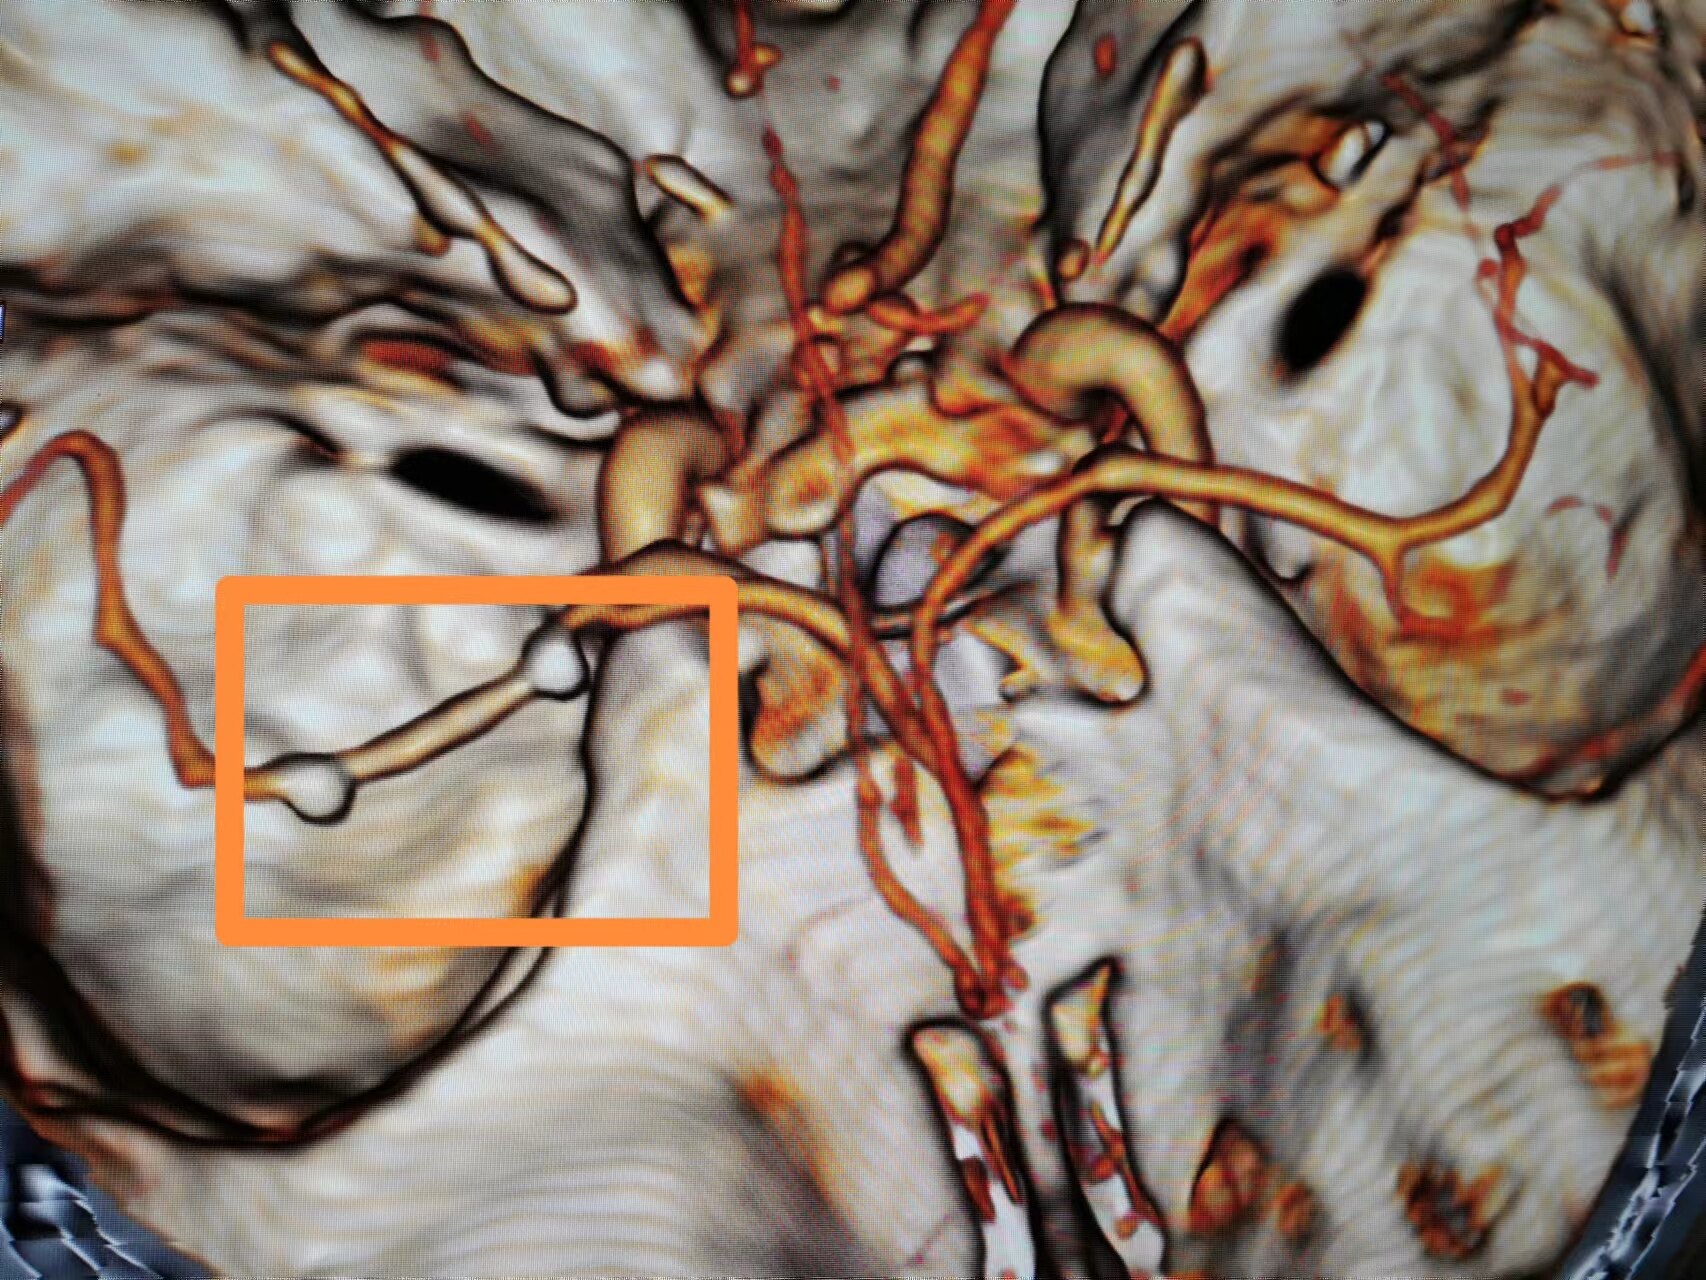

3、病变为长节段,M1上干已经闭塞;

5、粗大豆纹动脉的远端和近端都有一个狭长的血管变细

右侧MCA长节段血管变细狭长

长节段MCA血管狭长变细,尤以近端为重

乍一看血管似乎还可以

重建的形态

血管直径测量

血管形态

放大后仔细观看,近端有局限性血管变细,并见双腔征

另外时相远端也隐约局限性变细